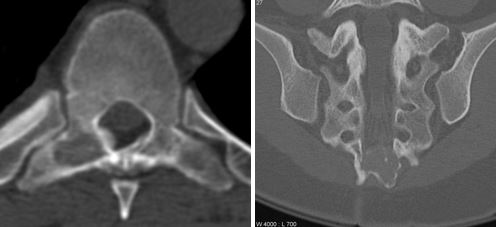

Доброкачественные опухоли

Опухолевые процессы в позвоночных тканях встречаются достаточно редко, и представляют собой аномально разросшиеся клетки спинного мозга и других структур – костей, хрящей и т. д. Доброкачественными называют образования с низким риском метастазирования, но, тем не менее, они способны вызывать компрессию нервных окончаний и внутренних органов, из-за чего серьезно нарушаются их функции.

Опухоли позвоночника

Таблица. Наиболее распространенные опухоли позвоночника.

| Разновидность опухоли | Особенности |

|---|---|

|

Остеоидная остеома |

Вид новообразования, который встречается примерно в 10% случаев всех опухолей позвоночного столба. Плохо диагностируется при рентгене, но четко определяется с помощью КТ и МРТ, хорошо поддается лечению и редко рецидивирует. |

Остеобластома |

Разновидность остеоидной остеомы, которая не вырастает более чем на 2 см, локализуется на задней части позвонков, обладает достаточно ярко выраженной симптоматикой и имеет склонность к появлению на тот самом месте. |

Аневризматическая костная киста |

Новообразование чаще всего встречается в шейном отделе, но может наблюдаться и в поясничном. Обычно появляются у подростков в пубертатный период, лечатся преимущественно оперативным путем. |

Гигантоклеточная опухоль |

Относятся к доброкачественным новообразованиям, но иногда могут быть крайне агрессивными, и распространяться на близлежащие ткани. Чаще всего возникают у людей в возрасте от 20 до 40 лет, излюбленное место локализации – передняя поверхность позвонков. Гигантоклеточные опухоли требуют осторожного подхода к лечению, иначе возможна малигнизация (озлокачествление) и серьезные последствия для здоровья. |

Энхондрома |

Образования, которые состоят из хрящевой ткани, могут отрицательно воздействовать на структуры позвоночника и спинной мозг. Отличается активным ростом, в редких случаях возможно перерождение опухоли в злокачественную – хондросаркому. |

Нащупать доброкачественные опухоли позвоночного столба под кожей достаточно сложно – это возможно только при разрастании новообразований до достаточно больших размеров или при локализации его в определенной части позвонка. Первый признак заболевания – неприятные ощущения разной интенсивности, который можно снять нестероидными противовоспалительными средствами или анальгетиками. Если опухоль давит на нервные окончания и спинной мозг, возможны неврологические симптомы – нарушения чувствительности и двигательной активности, головные боли, ухудшение концентрации внимания, быстрая утомляемость.

Остеобластома позвоночника